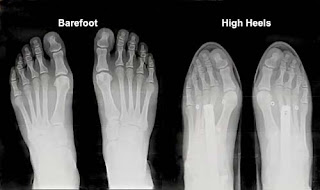

What if they’re a handicap or a fitness indicator like a risky bird call or a

peacock’s tail? The hampered, painful locomotion signals to potential mates how

badass the high heel wearer is. “We will have badass kids!” say high heels.